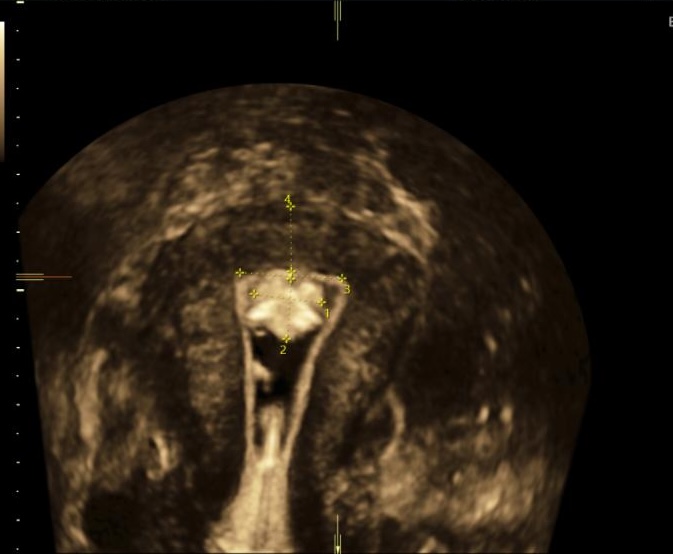

Lors du bilan de fertilité, je réalise:

- Une échographie pelvienne entre le 2ème et le 5ème jour des règles afin de vérifier que votre utérus est normal en 2D et reconstruction 3D, évaluer votre réserve ovarienne en réalisant le Compte des Follicules Antraux (CFA), vérifier que vos ovaires sont accessibles à une ponction d’ovocytes, et m’assurer de l’absence d’anomalie des trompes.

- Cette échographie peut être couplée à une hystérosonographie, réalisé dans ce cas entre le 6ème et le 12ème jour du cycle. L’hystérosonographie est l’injection de sérum physiologique dans l’utérus par voie vaginale pendant l’acquisition échographique 3D de votre utérus. Cette technique permet de rechercher des anomalies de la cavité utérine accessibles à la chirurgie et pouvant empêcher l’implantation d’un embryon ou le bon déroulement d’une grossesse ( fibromes, polypes, cloison utérine, synéchies).